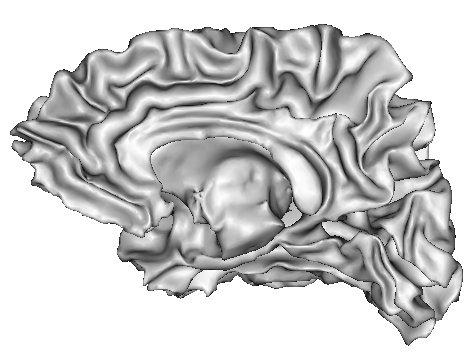

Imagine that a cerebral hemisphere has been split in two, and that white matter has been removed. The cortical surface can then be visualised from the inside:

This point of view helps to understand he skeletonization effect:

The skeleton is made up of the the brain hull and of the numerous surfaces medial to the folds: